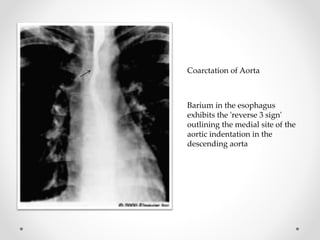

Barium in the esophagus

exhibits the 'reverse 3 sign'

outlining the medial site of the

aortic indentation in the

descending aorta

Coarctation of Aorta

Barium in theesophagus exhibits the 'reverse 3 sign' outlining the medial site of the aortic indentation in the descending aorta Coarctation of Aorta